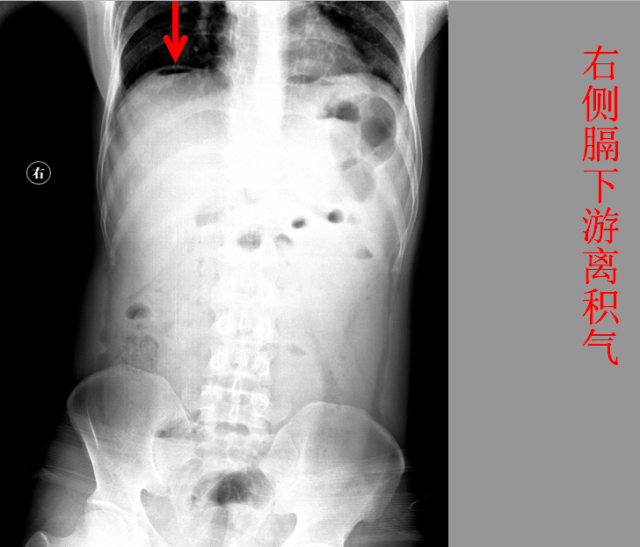

急腹症篇